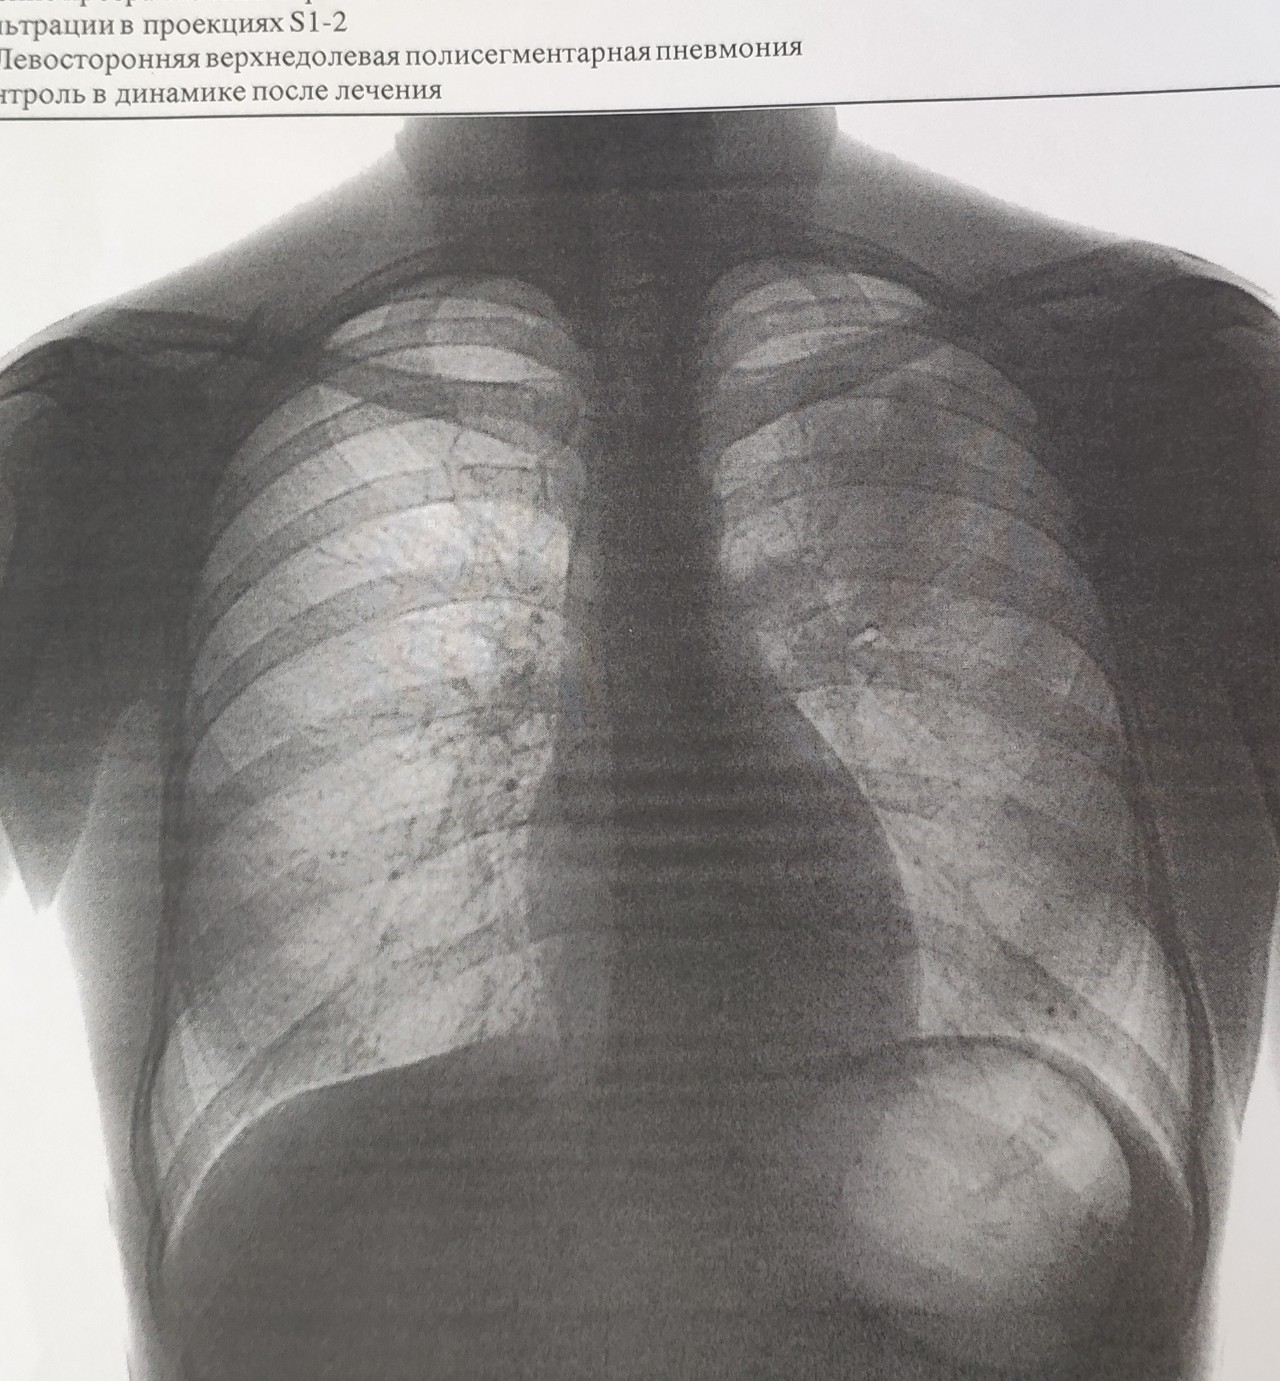

Снимок грудной клетки здорового ребенка: примеры и диагностика

Раздел: Мудрость в объективе